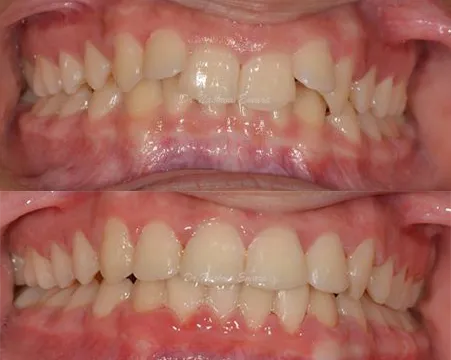

Orthodontics